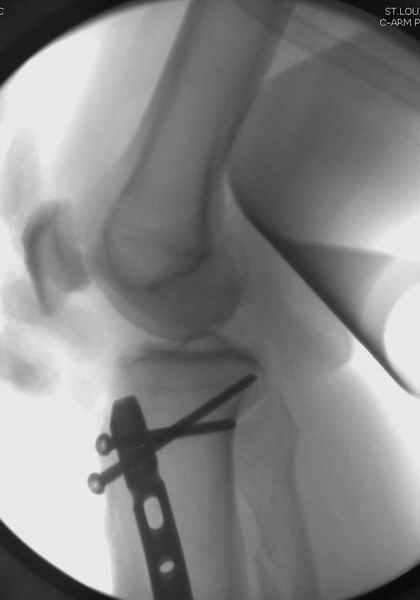

Здесь мы использовали новый Synthes Nail с дополнительными дырками, в проксимальной части 4: по две косых и поперечные (один стандартный а другой динамический), в дистальной части две поперечные, прямая и косая. Вес больного более 120 кг, нагрузку начнем через месяц.